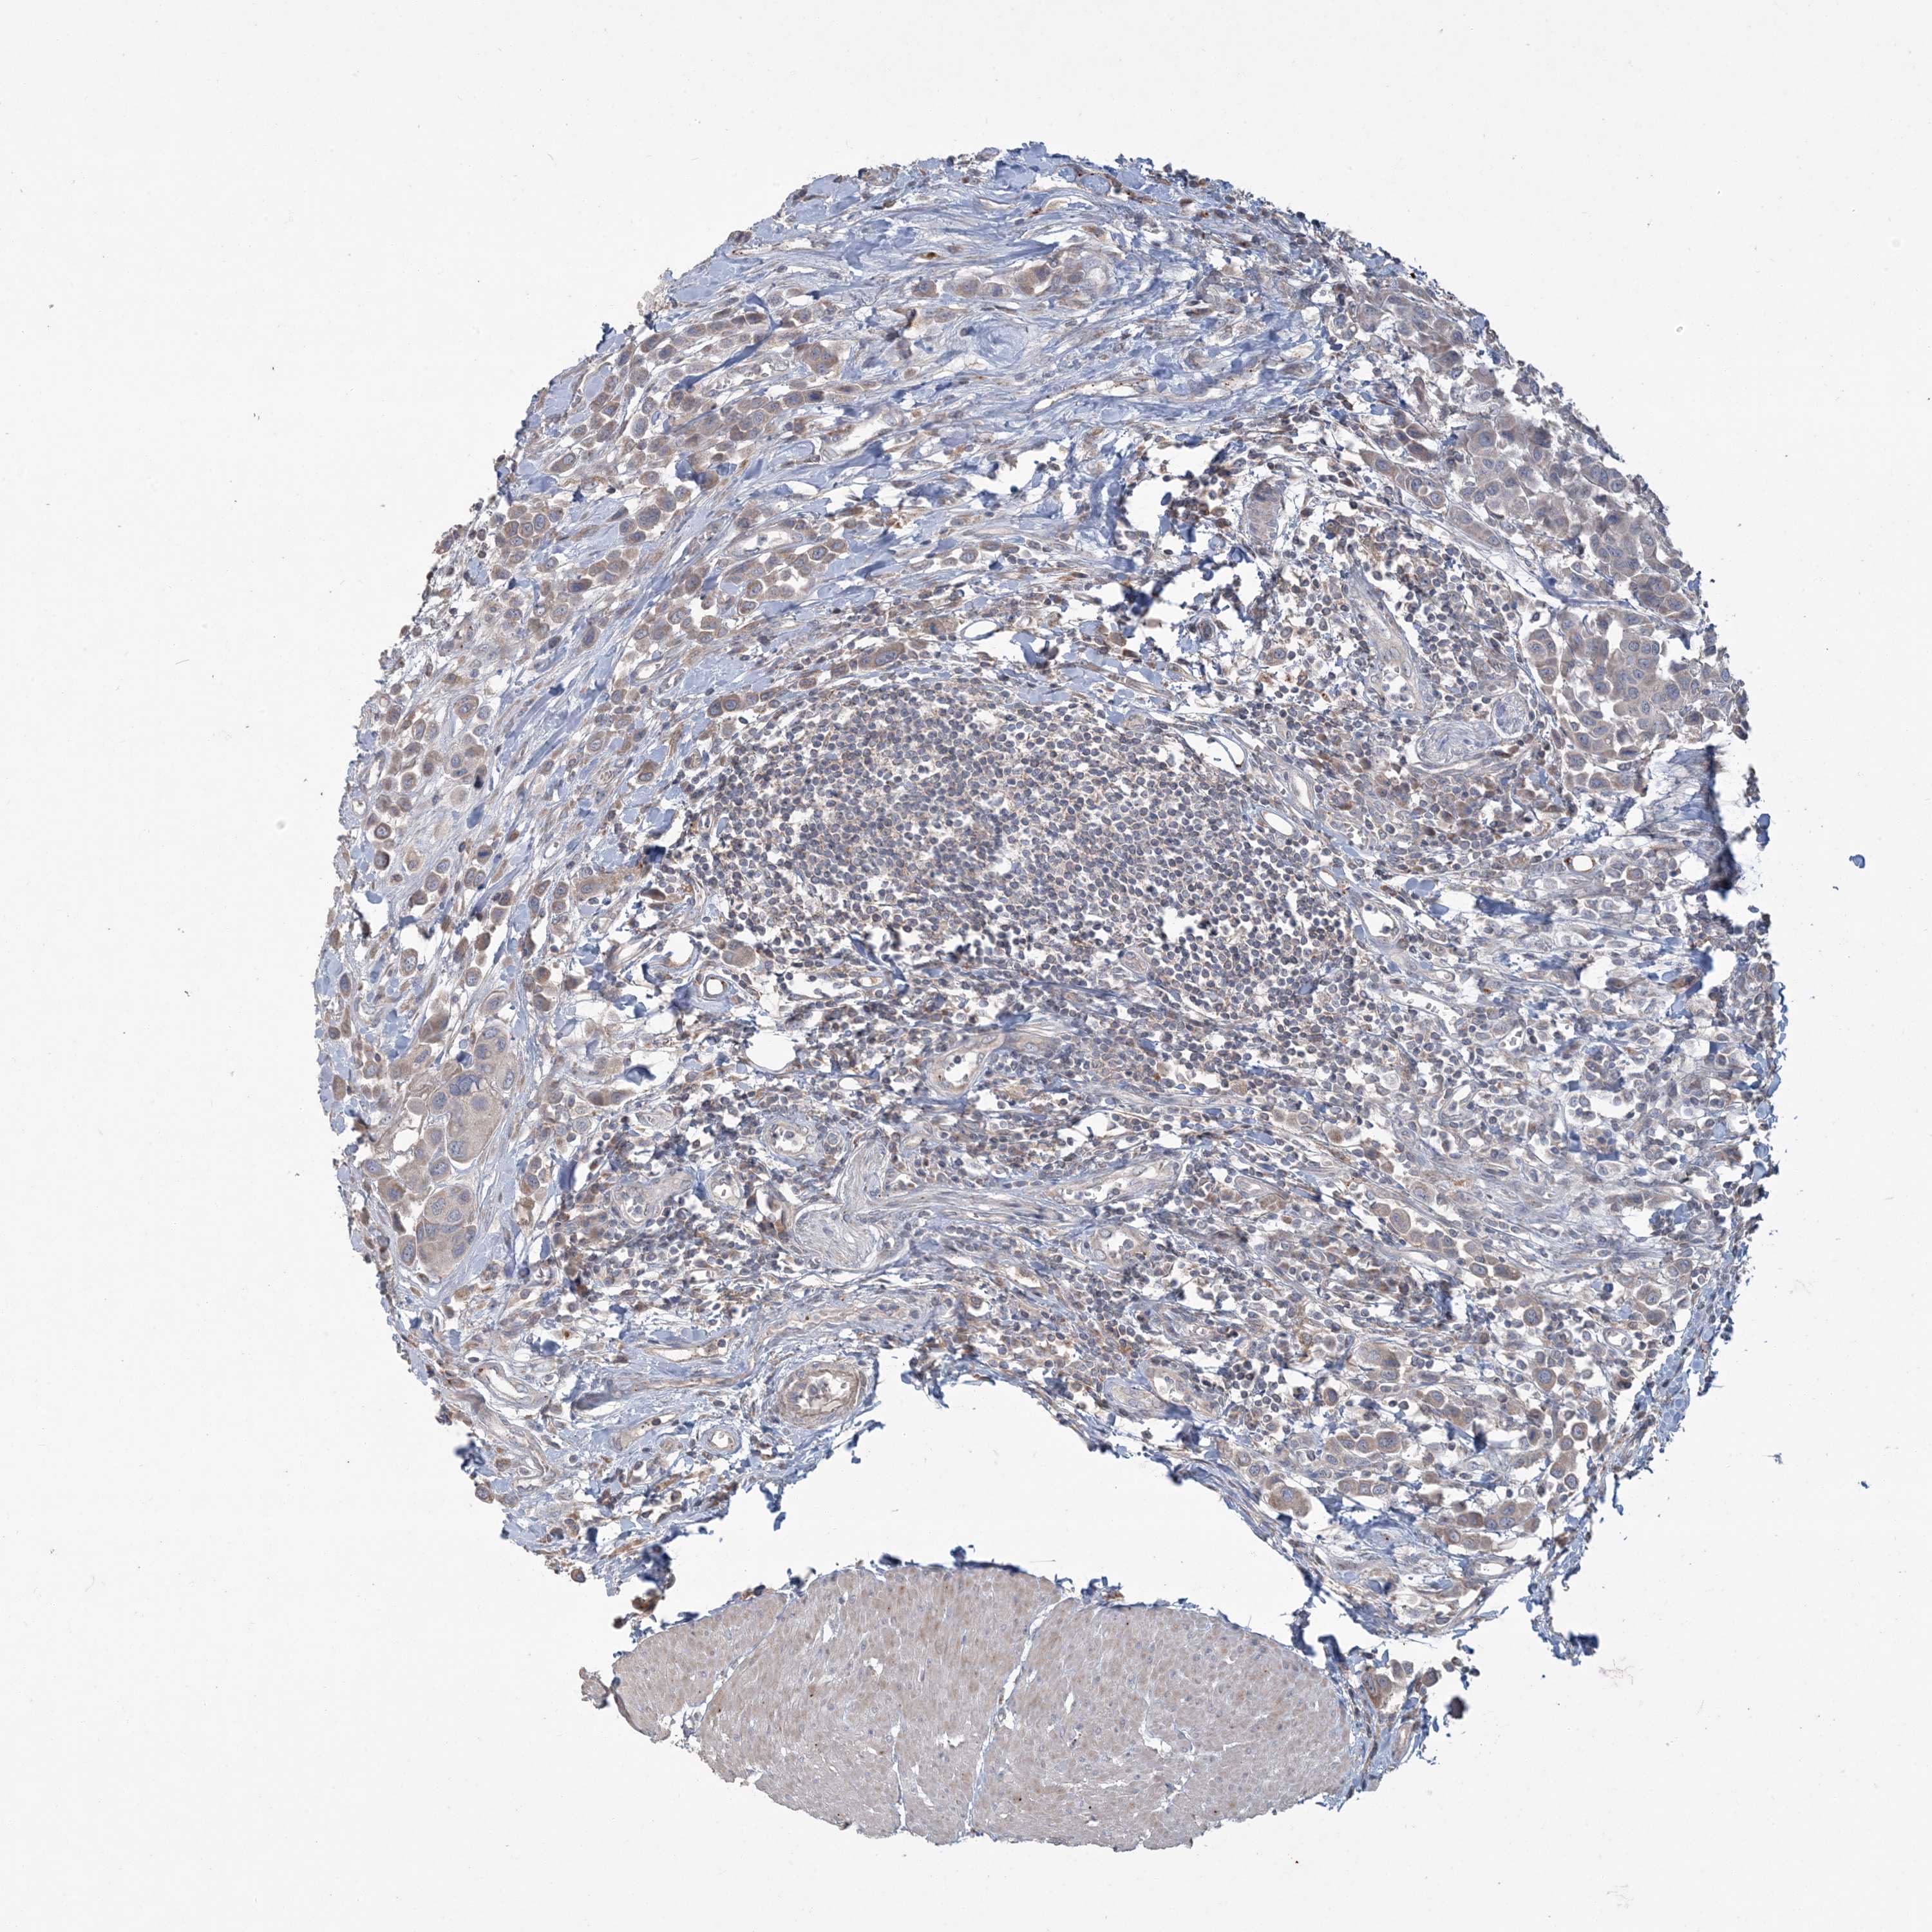

UROTHELIAL CANCER - Protein expressioni

A mouse-over function shows sample information and annotation data. Click on an image to view it in a full screen mode. Samples can be filtered based on level of antibody staining by selecting one or several of the following categories: high, medium, low and not detected. The assay and annotation is described here.

Antibody stainingi

Antibody staining in the annotated cell types in the current human tissue is reported as not detected, low, medium, or high, based on conventional immunohistochemistry profiling in selected tissues. This score is based on the combination of the staining intensity and fraction of stained cells.

Each image is clickable and will lead to virtual microscopy that enables deeper exploration of all samples and also displays staining intensity scores, fraction scores and subcellular localization as well as patient and tissue information for each sample.

Antibody HPA029143

Antibody CAB034164

Urothelial carcinoma, Low grade

Urothelial carcinoma, High grade